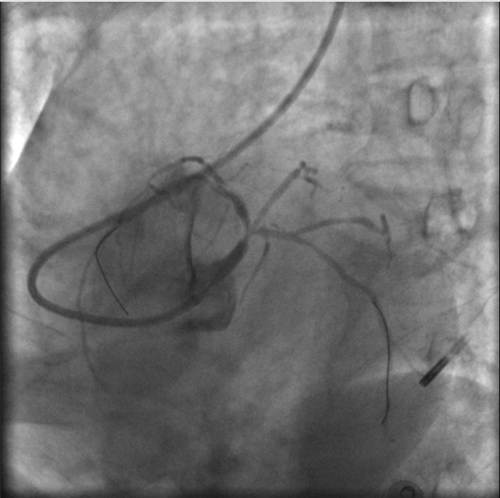

患者在IABP支持下病情相对稳定,血常规监测提示患者血小板呈进行性下降,上级医院专家建议尽快再次手术。心血管内科团队医护主动放弃休假,于5月2日再闯关。

因右侧肱动脉狭窄、股动脉一侧已植入IABP,徐主任这次选择了经左侧桡动脉入路手术。患者主动脉弓扭曲,导管操控十分困难,但依然没有难住有经验的石医心血管人,他们小心翼翼操控导管、导丝到位。

左冠血流保持通畅

确认左冠血流保持通畅,大家悬着的心才稍稍放下。

根据IVUS检查结果,在前降支近中段至左主干植入3枚支架,充分扩张后,狭窄完全解除,血流恢复通畅。

植入3枚支架,血流恢复通畅